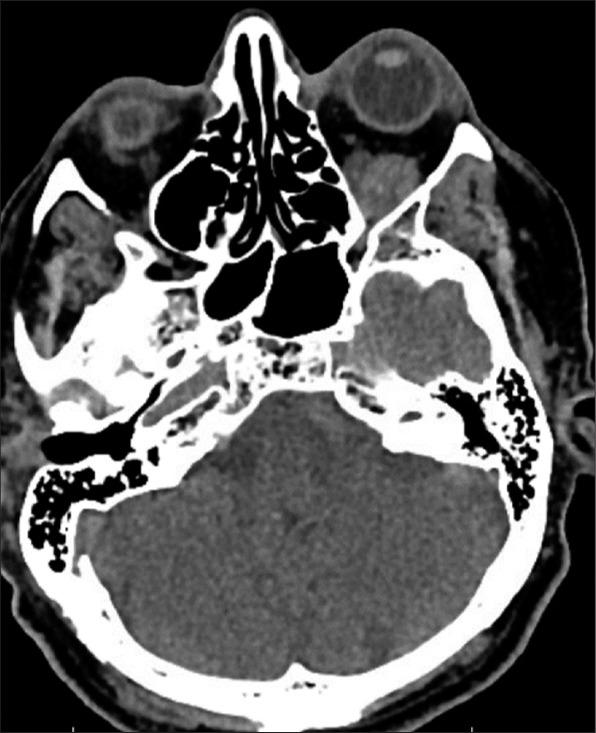

We report a case of a 74-year-old male with progressively painful unilateral proptosis. Imaging revealed the presence of an orbital mass compatible with a thrombosed orbital varix of the inferior ophthalmic vein in the left inferior intraconal space. The patient was medically managed. On a follow-up outpatient clinic visit, he demonstrated remarkable clinical recovery and denied experiencing any symptoms. Follow-up computed tomography scan showed a stable mass with decreased proptosis in the left orbit consistent with the previously diagnosed orbital varix. One-year follow-up orbital magnetic resonance imaging without contrast showed slight increase in the intraconal mass.